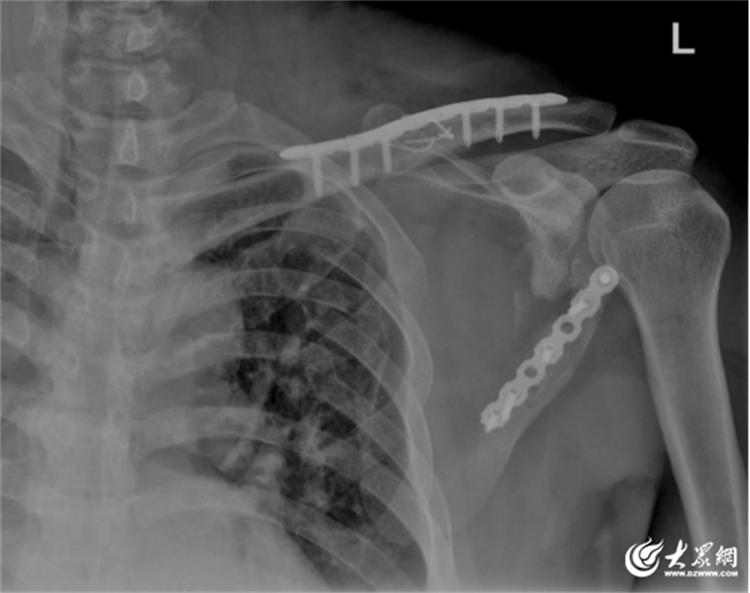

面对挑战,青岛市城阳人民医院创伤骨科(手足外科)团队联合北大人民医院骨科专家付中国教授,依托先进三维影像技术精密术前规划,创新采用经肩胛骨外侧缘的微创入路。术中仅通过约5厘米切口,在完美保护旋肩胛动脉等前提下,实现粉碎骨折块的解剖复位,并以个体化设计钢板实现坚强固定。术后影像显示关节面平整度完美恢复,为患者肩关节功能重建奠定最优基础。

青岛市城阳人民医院创伤骨科(手足外科)副主任、主任医师黄佳军表示:“肩胛骨骨折累及关节盂,手术难度极大,既要避免损伤周围神经血管,又要确保肩关节功能重建,此次微创手术的成功应用,显著减少了患者创伤,为后期康复奠定基础。”